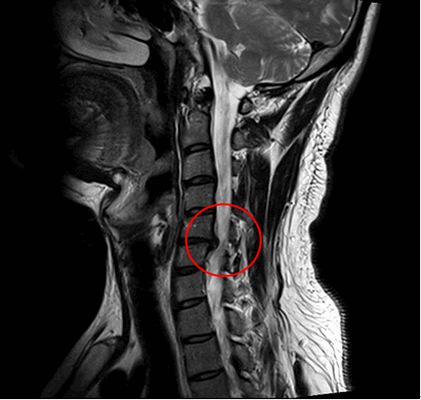

- Корпэктомия: иногда материал диска встает между телом позвонка и спинным мозгом и не может быть удален только с помощью дискэктомии. В других случаях, между телом позвонка и спинным мозгом образуются костные шпоры (остеофиты). В этих ситуациях для доступа к диску может потребоваться удаление всего тела позвонка. Эта процедура называется corpectomy (corpus- означает, а ectomy - удаление).

Среди существующих хирургических методик, используемых с целью восстановления функциональности шейного отдела, наибольшее распространение обрели декомпрессионные тактики. Их применяют при компрессионном синдроме, то есть когда патологический дефект, возникший в пределах С1-С7 позвонков, производит давление на нервные корешки, артерии, спинной мозг и прочие структуры в соответствующей зоне. С целью декомпрессии довольно часто задействуются следующие методики: